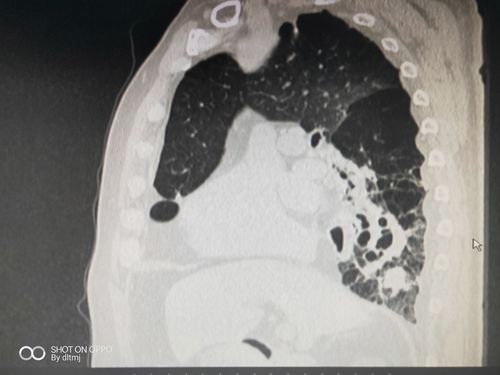

支气管扩张痰液分层

支气管扩张痰液分层,支气管扩张杵状指

支气管扩张,自发性气胸,肺复张术后,痰液潴留,经支气管镜吸痰处理后

支气管扩张关键要把痰咳出来,淤在里面会反复感染.

支气管扩张的ct图片

支气管扩张痰液分层图

支气管扩张的痰液图

支气管扩张图片

支气管扩张图片样子